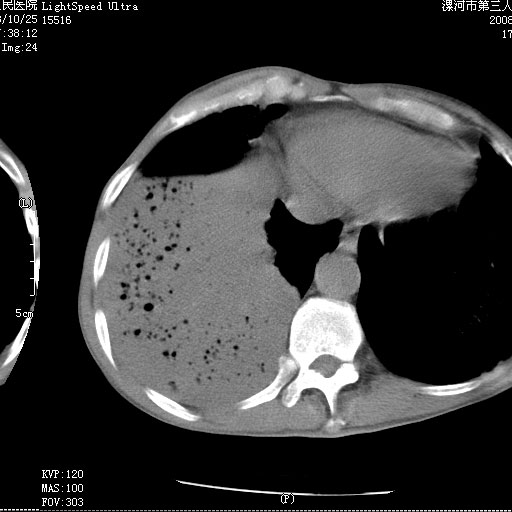

m 老年 发烧、呼吸困难,慢支、肺气肿多年;记的那次是下午大概17:38做的,晚上窒息死亡。

上面的层面就慢性支气管炎肺气肿、肺大泡,别的没有什么、也就不传了。

当时我怀疑:1、阻塞性肺不张早期 2、肺脓肿早期,望老师们发表意见

病灶边缘清---多个含气小腔---近端未见通畅气管影-----支持-----慢性肺脓肿继发阻塞性肺不张

阻塞性肺不张原因-----脓液未排出

1、右侧脓胸;2、copd;

3、细支气管肺泡癌可以排除,病变以斜裂为界,呈大片状高密度影,内可见多发小气泡,表明有产气杆菌感染所致,内无明显的支气管“枯树枝征”表现,再结合其临床改变(细支气管肺泡癌临表表现重、影像表现轻)所以不符合细支气管肺泡癌(炎症型)的改变。

病变按肺叶分布,病变内可见多个小空腔影,未见充气支气管影,中间段支气管管腔肺窗示密度欠均匀,下肺支气管分叉处基底段支气管隐约可见,未见明显狭窄,中叶支气管通畅,

考虑:阻塞性肺炎伴小脓肿形成可能性大。(痰栓可能性大)

右下肺实变,内有弥漫分面小气泡而无支气管征,叶间裂前移,呈臌大之形,而无收缩之状,兼纵隔稍左行移,故。不支持不张,倒支持大叶肺叶,如楼上所说,小气泡不象残留之肺,不可以考虑产气菌感染吗。

阻塞性肺炎,肺脓肿形成。依据,右下支气管不通,大片实变形内可见小气泡。不支持肺不张。